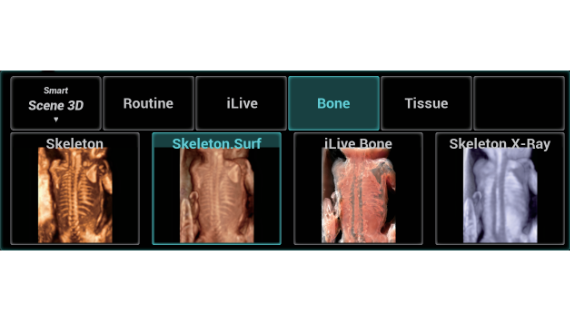

Gambar Klinis